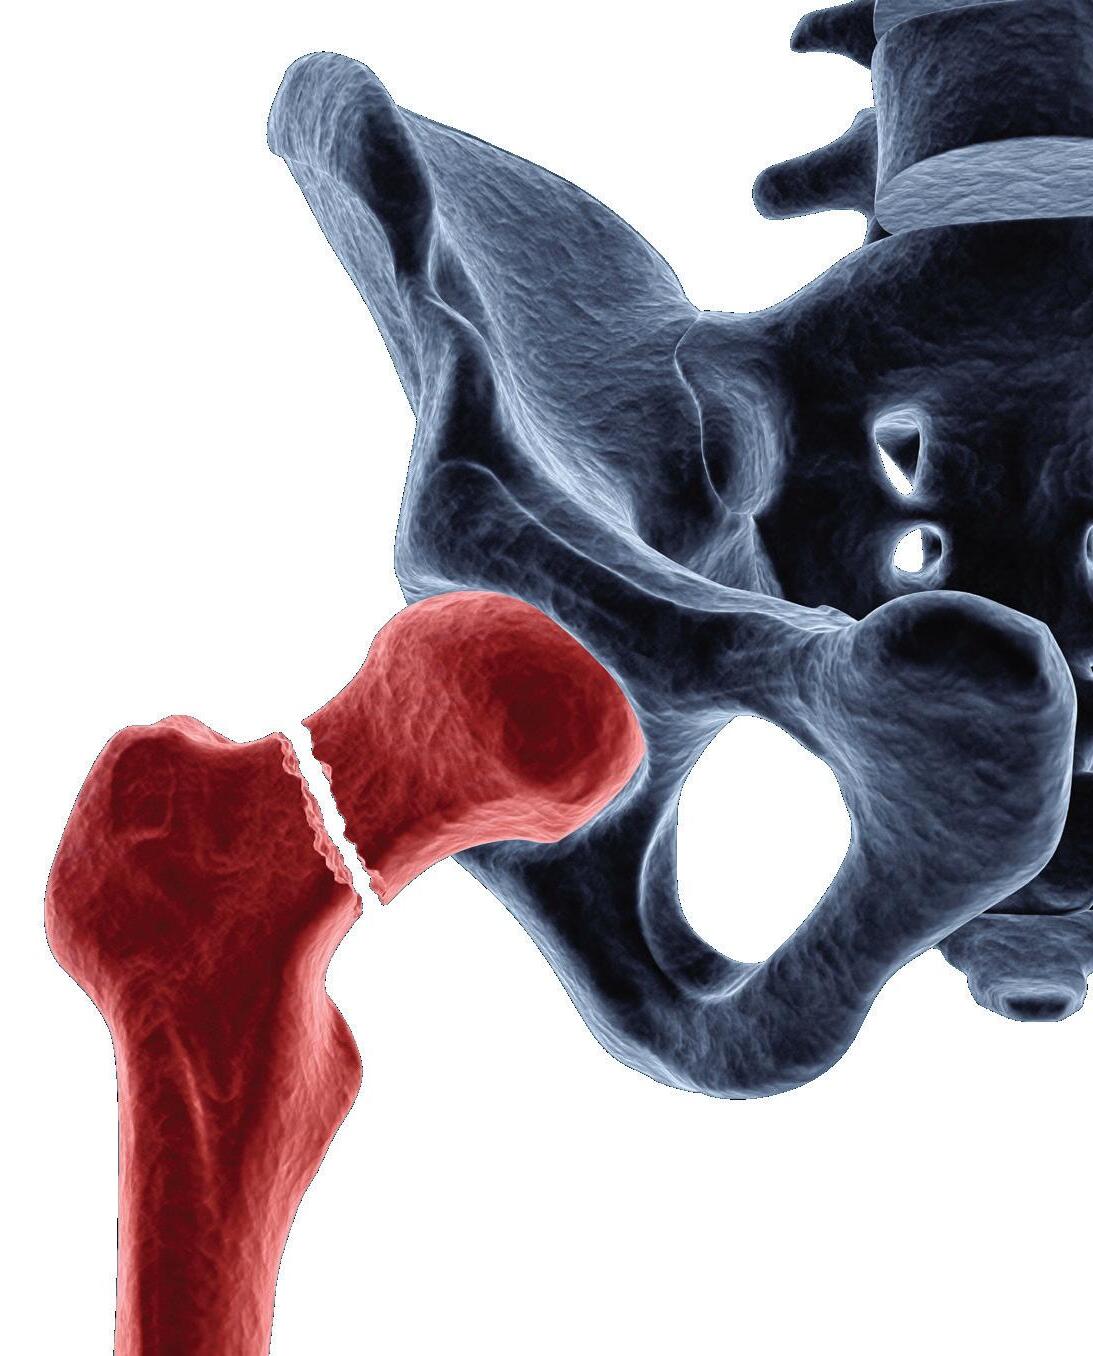

REDUCE RISK FOR INFECTION

Reduction of infection risk* using dual antibiotic-loaded bone cement in high risk patients

in primary hip & knee arthroplasty in fractured neck of femur in aseptic revision TKA